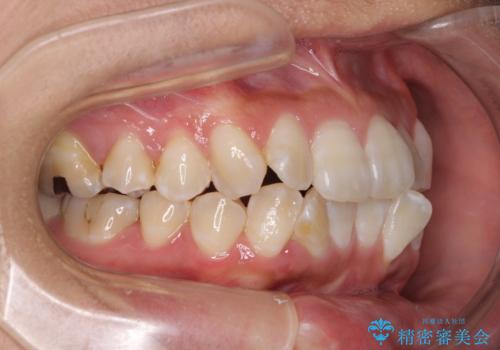

- 上下の前歯のでこぼこを気にして来院された患者様です。

職場の都合により、表側のワイヤー装置や着脱作業が頻繁なマウスピース矯正は困難とのことで、全く目立たない裏側矯正装置を用いて口元を整えることとしました。

途中転勤や出産があり、通院できない期間が長くありましたが、無事に歯列を整えることができました。